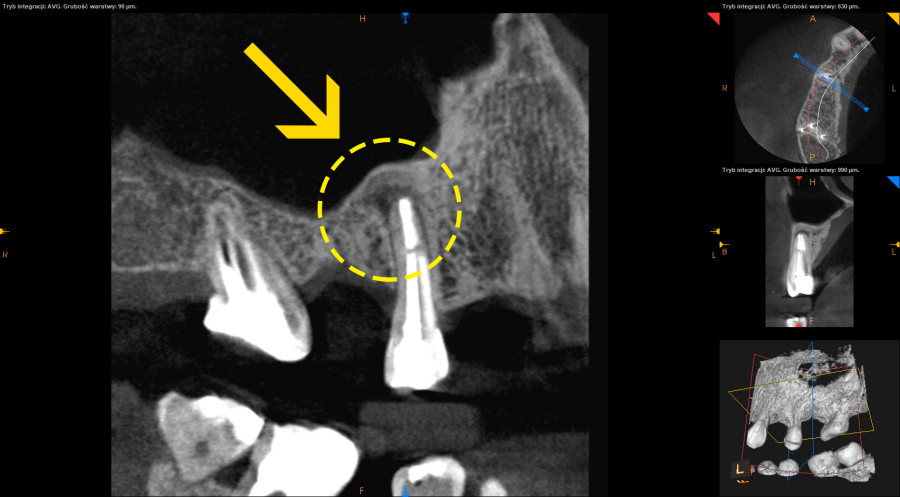

- Rozległe zmiany okołowierzchołkowe w kości goją się w okresie nawet do trzech lat i w tym czasie pacjent pozostawałby bez uzupełnienia protetycznego.

- Wykonanie nowoczesnej diagnostyki pozwoliło na znacznie szybszą ocenę gojenia w stosunku do prześwietleń takich jak ortopantomogram lub radiowizjografia i skróciło okres obserwacji gojenia.